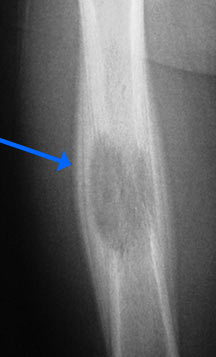

- May arise from any bone and any site within a bone (epiphyseal, metaphyseal, diaphyseal)

- Radiographically variable appearance: may appear benign (geographic) or malignant (permeative or moth eaten)